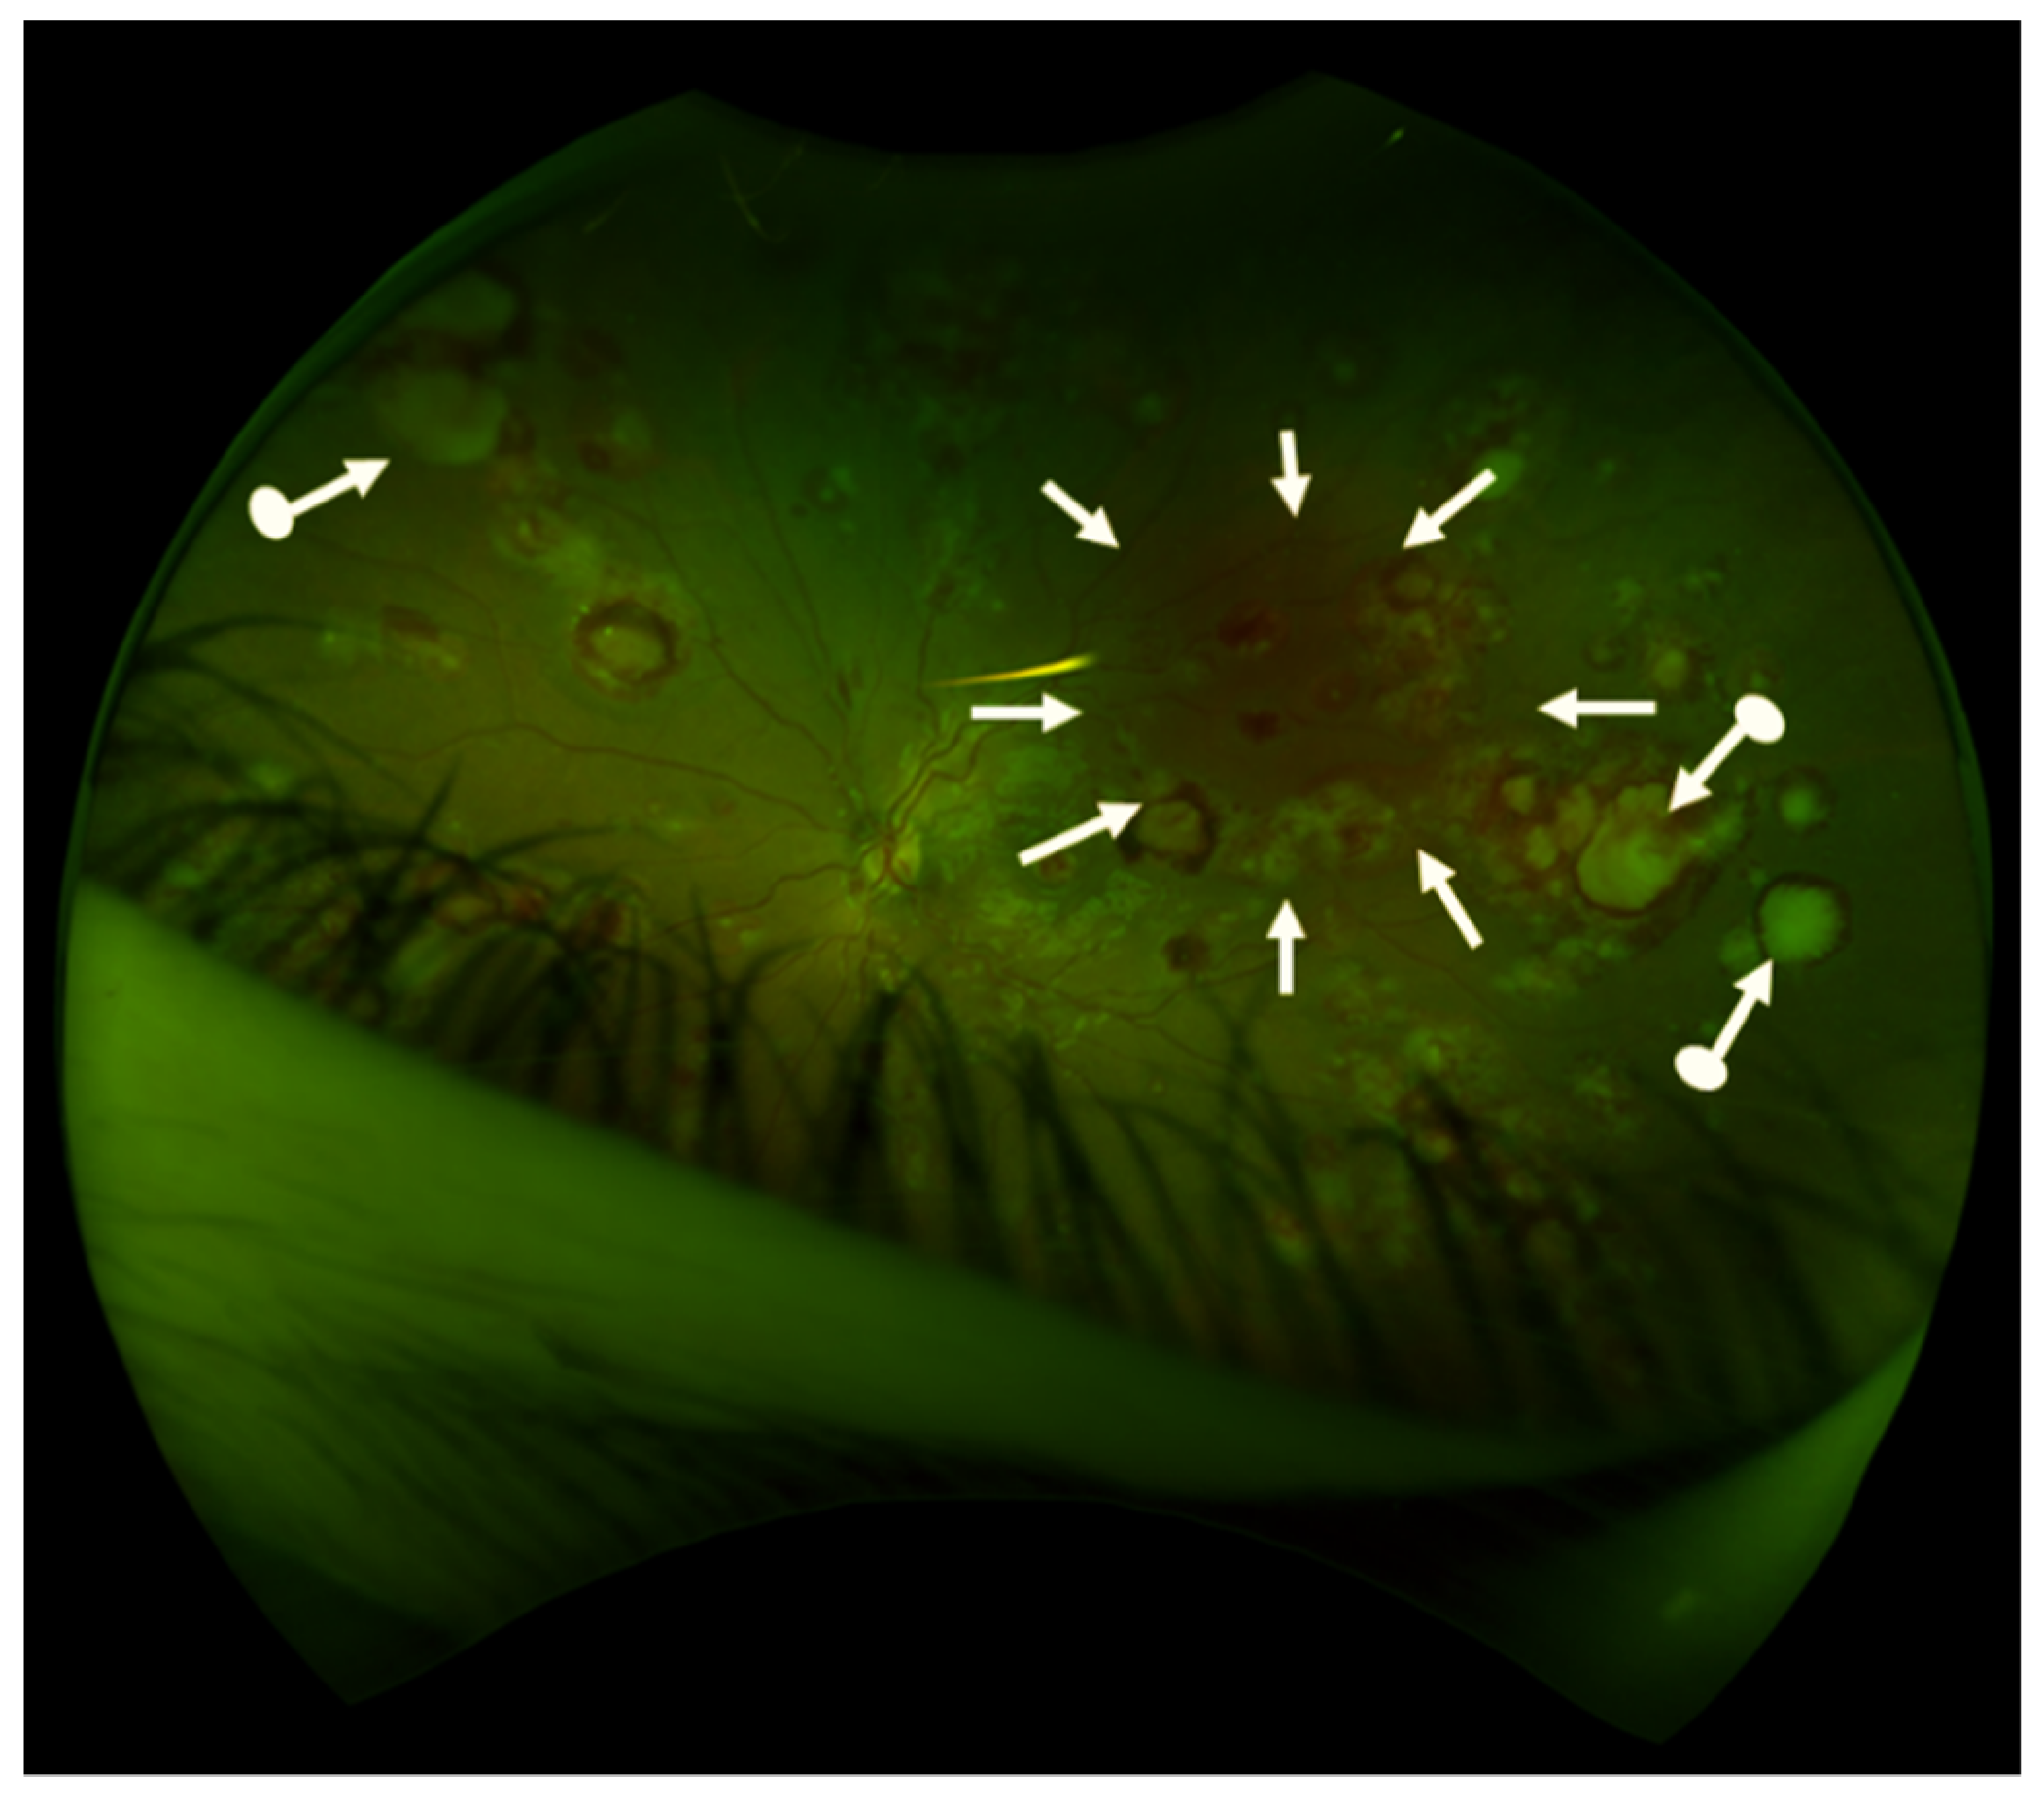

- Kurosawa, H.; Tanizawa, A.; Tono, C.; Watanabe, A.; Shima, H.; Ito, M.; Yuza, Y.; Hotta, N.; Muramatsu, H.; Okada, M.; et al. Leukostasis in Children and Adolescents with Chronic Myeloid Leukemia: Japanese Pediatric Leukemia/Lymphoma Study Group. Pediatr. Blood Cancer 2016, 63, 406–411. [Google Scholar] [CrossRef] [PubMed]

- Chen, B.; Yan, X.; Zhang, X.; Yang, H. Leukostasis Retinopathy: An Uncommon Visual Threatening Complication of Chronic Myeloid Leukemia with Severe Hyperleukocytosis - A Case Report and Review of the Literature. Ind. J. Ophthalmol. 2018, 66, 1871–1874. [Google Scholar]